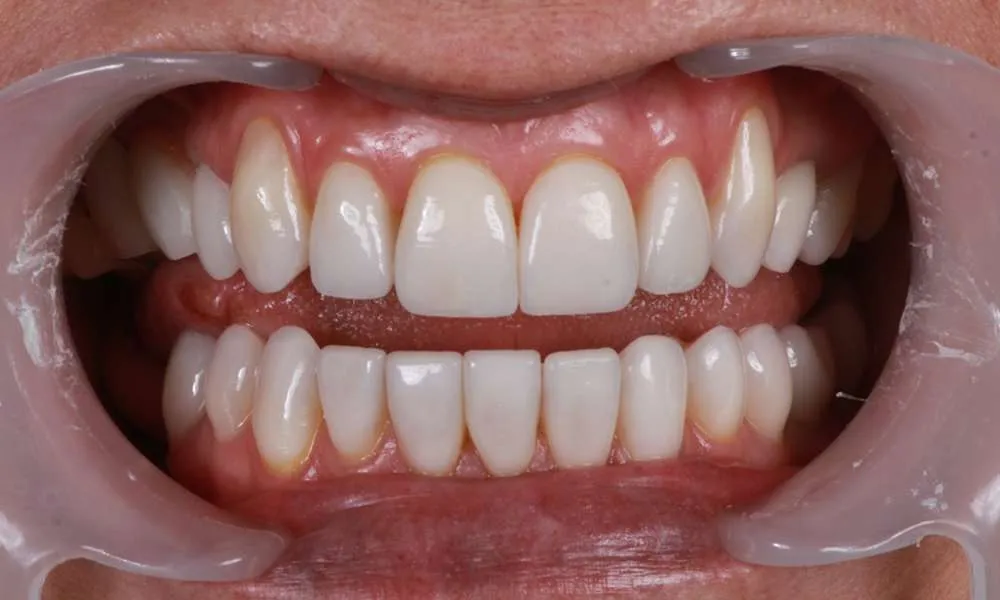

Real Stories, Real Results: Case Studies Showcasing How Our Personalized Approach Transforms Smiles and Lives

Ultra-thin veneers are crafted from high-quality materials that closely resemble the look and feel of natural teeth. The translucency and texture of these veneers mimic the appearance of real enamel, ensuring that your smile looks natural and aesthetically pleasing. Each veneer is custom-made to match the color, shape, and size of your existing teeth, blending seamlessly with your natural smile. This attention to detail ensures that your veneers are virtually indistinguishable from your natural teeth, providing you with a flawless, beautiful smile.

Witness the Remarkable Changes We Can Achieve

The process of getting ultra-thin veneers typically involves several steps. First, during the initial consultation, we will discuss your goals and take impressions and photographs of your teeth. Next, we will minimally prepare your teeth generally less than 0.5mm of preparation (sometimes little or no preparation is needed depending on the design). Then you'll leave with a 'trial smile' and temporary veneers in place, after which we'll have a follow-up appointment the next day for final evaluation of your temporary veneers for tweaks and fitting to help guide the lab to your custom smile. Your veneers are finally crafted in a premier dental lab. Finally you'll return to the office where your custom, ultra-thin veneers are bonded to your teeth using biocompatible materials. The entire process usually takes one to four weeks from start to finish depending on the lab and complexity of the case.